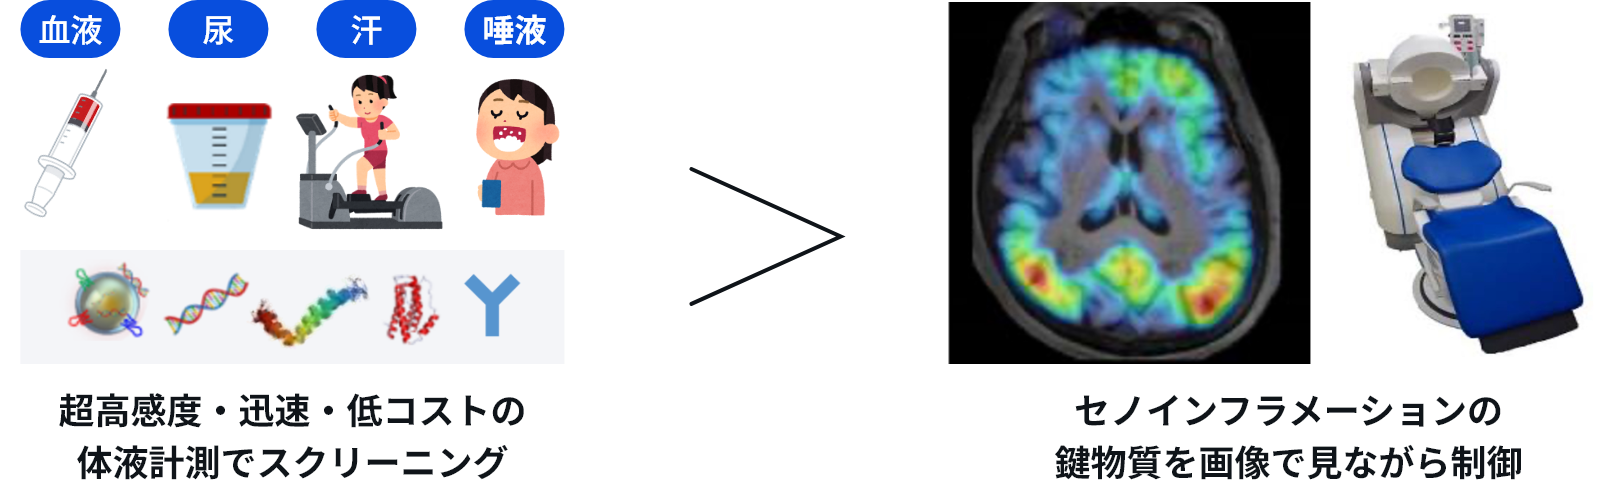

認知症は、主に脳内で生じる三つの有害な変化によって引き起こされると考えられます。すなわち、アミロイドβやタウといったタンパク質が異常な線維状の「ゴミ」として蓄積すること(脳タンパク質老化)、本来は脳を守る役割を担うグリア細胞が炎症を引き起こすこと、そして神経細胞やグリア細胞が老化することです。老化と炎症の二者が相互に増幅する「セノインフラメーション」に加えて、脳タンパク質老化が加わった三つ巴の「脳内セノインフラメーション」が認知症病態の本質といえます。本プロジェクトでは、「脳内セノインフラメーション」を駆動する鍵分子の同定と制御を目標としています。これらの鍵分子を標的として、血液検査や画像検査の小型・高効率化や、新規治療薬の創出を推進し、認知症を克服した健康長寿社会の実現を目指します。

認知症克服に最も有効な鍵物質を同定し、血液・画像検査で病態を評価する。

医療の実現鍵物質を可視化しながら介入し、治療薬や次世代サプリの有効性を検証する。

少量検体で鍵物質を簡便に検出し、エビデンスに基づく技術の社会実装を進める。